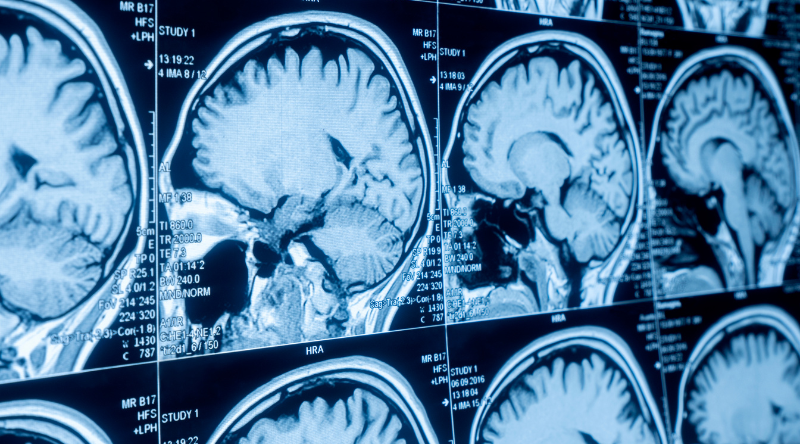

Brain Health & Cognitive Clarity